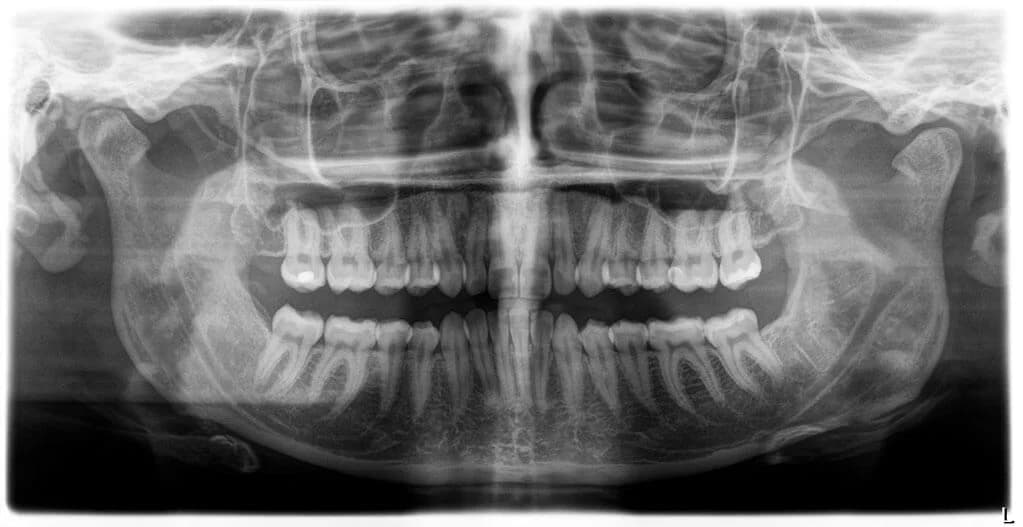

Die notwendigen Röntgenaufnahmen werden dank strahlungsarmer digitaler Durchführung erzeugt. Somit bekommen Patienten wesentlich weniger Strahlenbelastung zugemutet; besonders wichtig ist dies für unsere jungen Patienten.

Obwohl die Strahlenbelastung sehr gering ist, entstehen durch die moderne Multilayer-Technik gestochen scharfe Panoramaaufnahmen und Fernröntgenseitenbilder, sodass wir Ihre Zähne und Ihren Kiefer optimal beurteilen können.